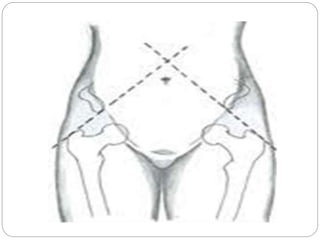

2. SHOEMAKER’S LINE

 Supine position:

 Line joined by connecting two points greater trochanter & ASIS

when extended up on both sides

1. May cross above the umbilicus in the midline – Normal

2. May cross below the umbilicus away from midline – opposite

unilateral supratrochanteric shortening

3. May cross in midline below the umbilicus – bilateral

supratrochanteric shortening

 Not useful in case of bilateral disease.

3. CHIENE’S LINE

Supine position:

The lines joining two ASIS & two greater

trochanter are usually parallel.

This is disturbed if one of the greater

trochanter is shifted upwards.

Useful in unilateral disease only.